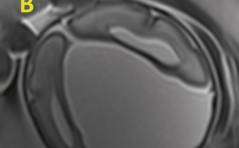

Auflösung Sonoquiz 04/18

Interhemisphärische Hirnzyste PDF Dokument